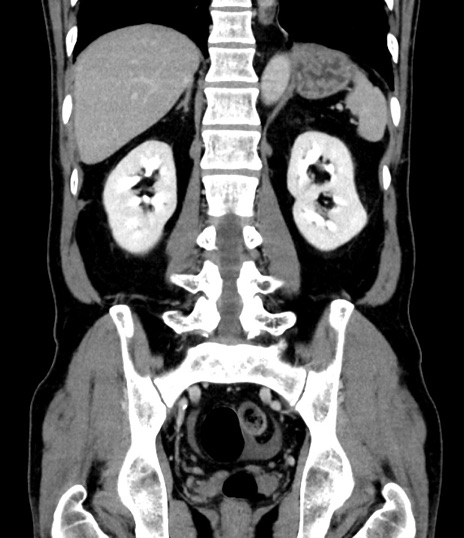

症例8(冠状断像)

【症例】 60歳代男性

【主訴】 黒色吐物

【現病歴】 4日前から嘔気自覚、2日前の朝食後にも嘔気あり、自分で手で嘔吐反射起こし嘔吐したところ血が混ざっていたため受診。

【既往歴】 5年前汎発性腹膜炎を伴う急性虫垂炎で手術、高血圧、前立腺肥大症、高脂血症

【身体所見】 腹部正中に手術癩痕あり 腹部平坦・軟圧痛なし膨満感あり

【データ】WBC 8400、CRP 4.54